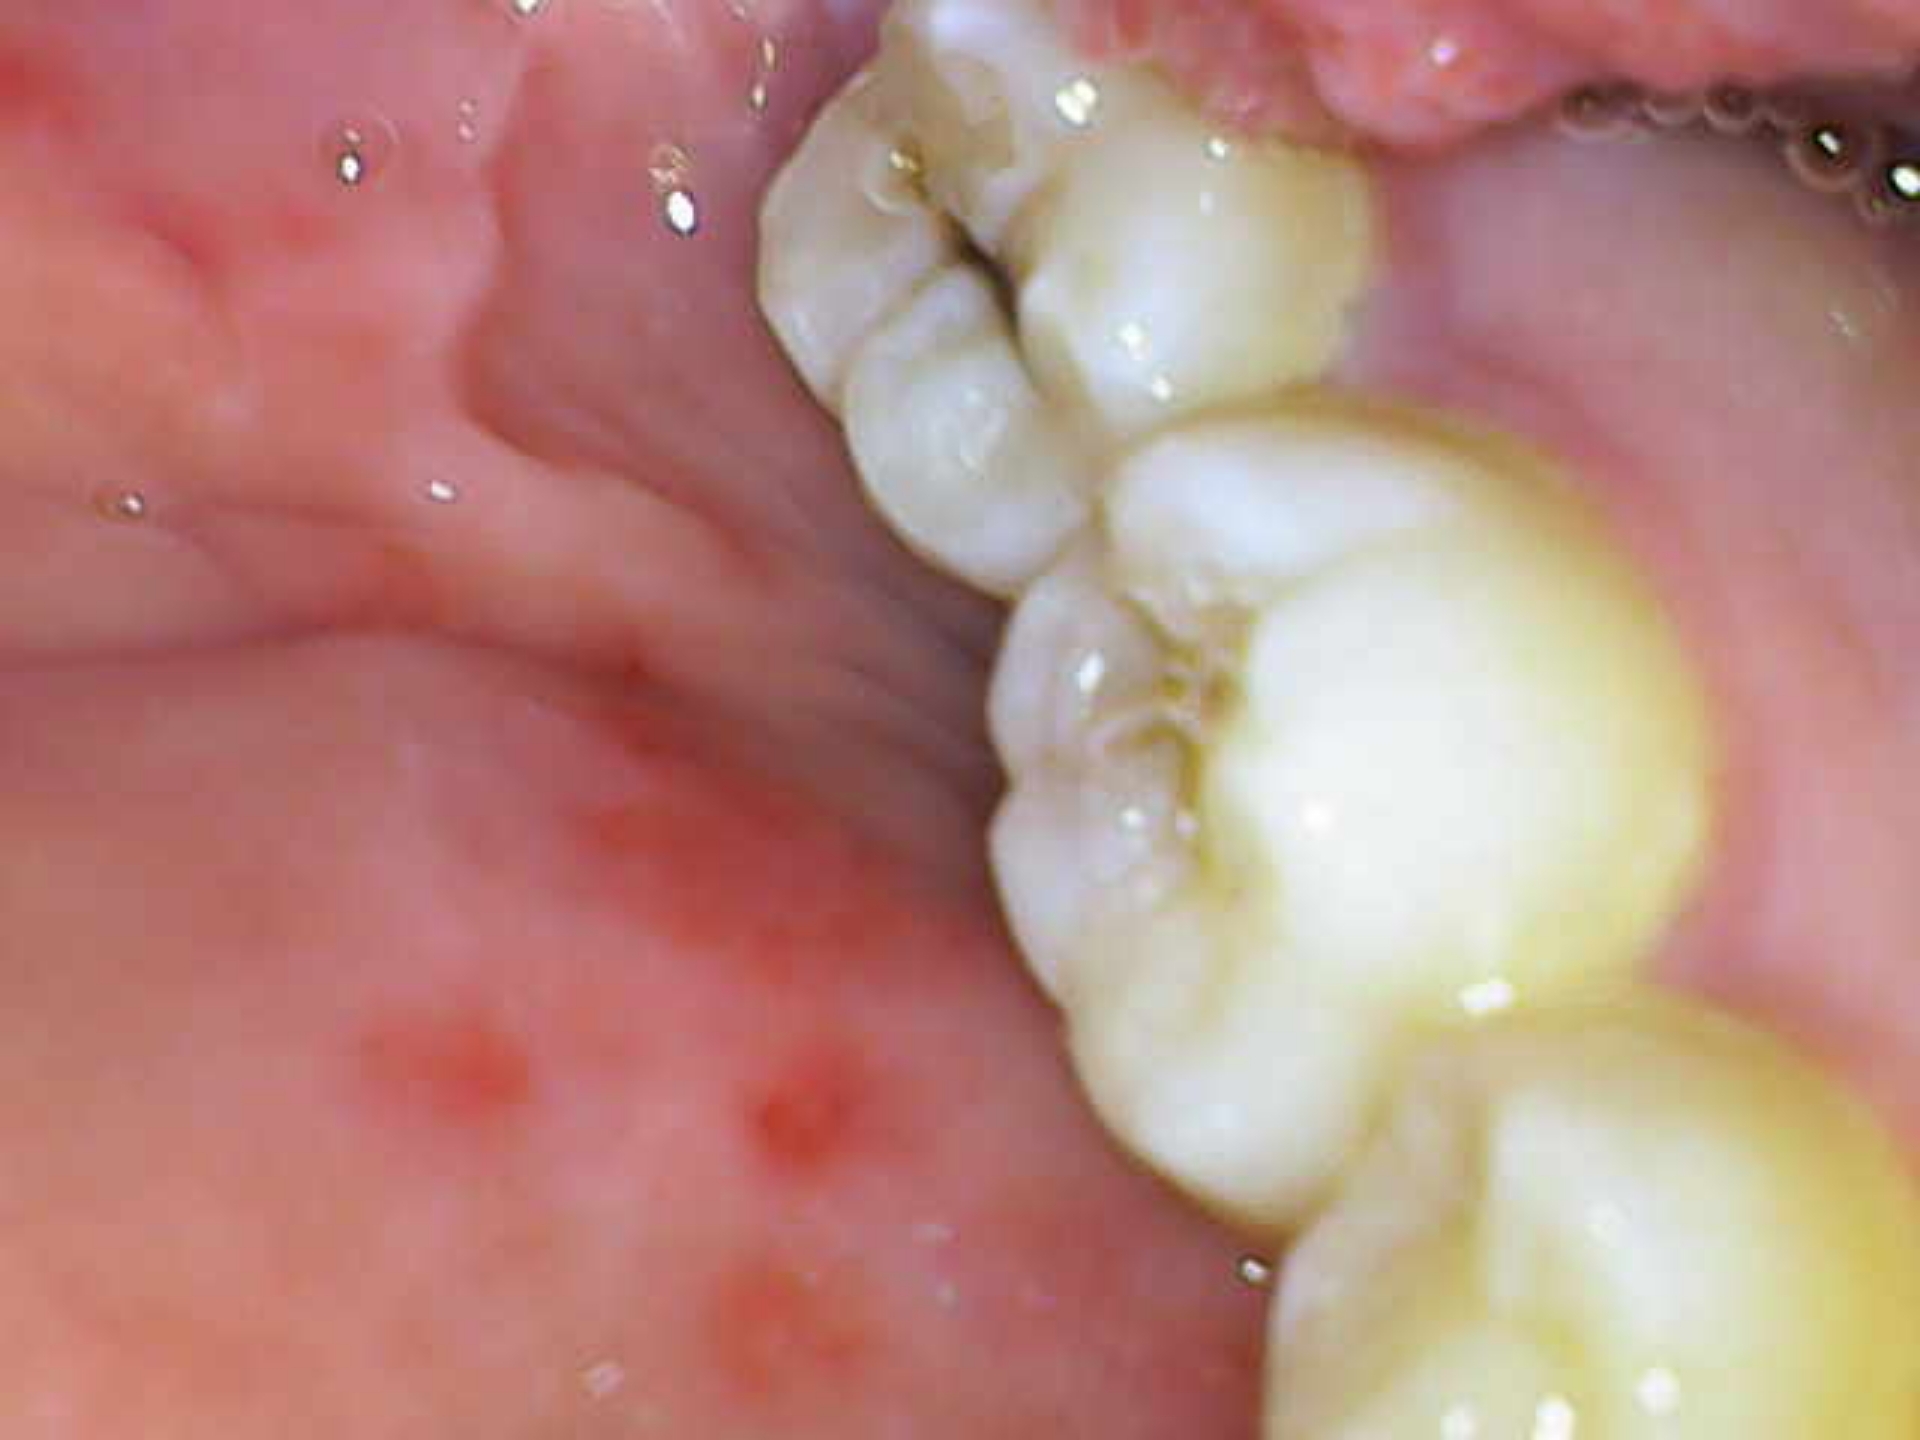

Десны, на месте где зубы в них входят такая вот хуйня, отметил рядом если не понятно. Это начало парадонтита или чего-то такого? Камень года 3 не ходил чистить, каюсь. Есть связь с камнем?

Аноним 09/09/25 Втр 12:47:10 1639465 110